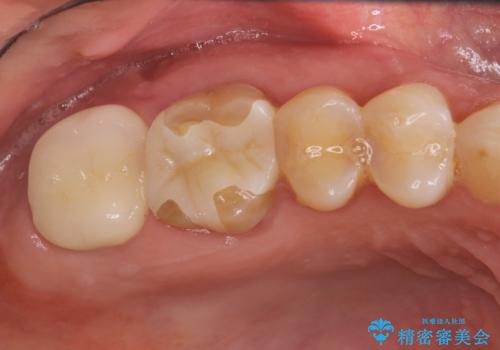

感染した奥歯 痛くて咬めない 根管治療→かぶせ物で痛みを取り除き、かみ合わせを回復する

- 古い詰め物を除去し、腐ってしまった神経を顕微鏡下で丁寧に処理する

すでに感染が根の先端まで及んでいたため、かなり強い痛みがありましたが、丁寧に根管治療をすることで内部を可及的に無菌化し、痛みが消失しました。